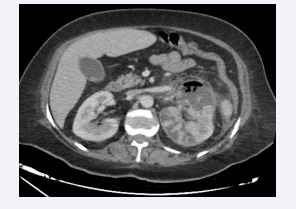

Axial section of an abdominal CT scan without intravenous  contrast injection, showing a left kidney with parenchyma reduced by  hydronephrosis, with air bubbles in the parenchyma and calyces. The  appearance is compatible with a class 2 left EPN according to Huang et al.

Figure 4: Axial section of an abdominal CT scan without intravenous contrast injection, showing a left kidney with parenchyma reduced by hydronephrosis, with air bubbles in the parenchyma and calyces. The appearance is compatible with a class 2 left EPN according to Huang et al.